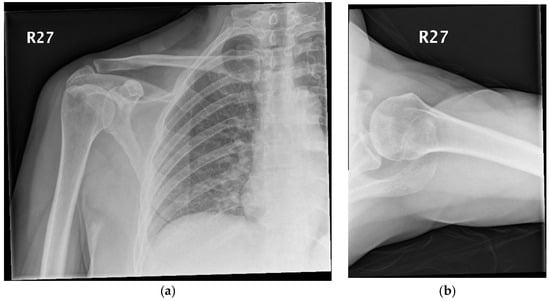

Prior to the operation, an MRI (magnetic resonance imaging) scan was requested to assess/confirm the presence of a collection within the joint. The MRI scan went on to demonstrate no collection within the shoulder joint; however, inflammation involving the right pectoral muscle approximately 8.8 cm in circumference was observed, suggesting pectoralis major pyomyositis (Figure 2a–c).

Diagnosis of pyomyositis involves having a low index of suspicion and working through a series of investigations. There are no set criteria; together, clinical judgement and physiological parameters as well as biochemical investigations can help to rule in (or out) such a diagnosis [9,10]. Mazur et al. found MRI to be 97% sensitive for diagnosing acute musculoskeletal infections [11]. Through this case we demonstrated how the MRI scan was vital to help to rule out a collection within the shoulder joint and to prevent unnecessary surgery. Equally, the MRI aided us in making our diagnosis and helped us to monitor the regression in the size of the collection.

Figure 2. (ac) Axial images demonstrating right pectoralis major pyomyositis.